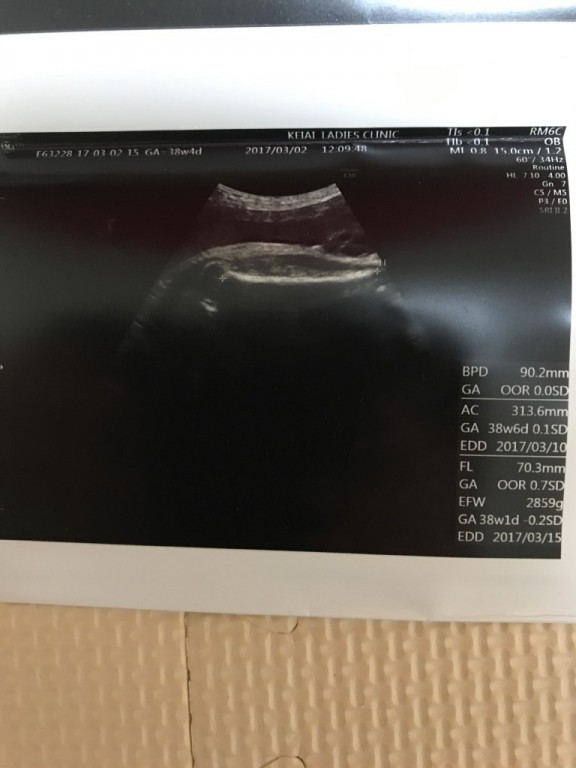

- 妊娠10ヶ月 37週0日 撮影日:2017年02月24日

- 妊娠10ヶ月 37週0日 撮影日:2017年02月24日

- 妊娠10ヶ月 37週0日 撮影日:2017年02月24日